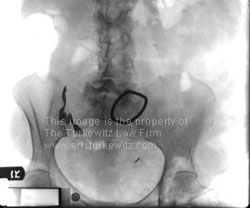

The x-rays and case summaries on this page are from New York medical malpractice lawsuits where surgical equipment was inadvertently left inside the patient at the close of surgery.

Retained sponges/lap pads and other instruments can result in serious conditions including sepsis, intestinal obstruction, fistula or abscess formation and adhesions. A secondary surgical procedure is often required for removal of the retained foreign object, often times with extended hospitalization to fight infection. This is a “never, ever” type of event since the surgical team is supposed to count all instruments and pads at the beginning of surgery and again at the end, to avoid this very problem.

‡ This is a pad made from several layers of gauze folded into a rectangular shape and used especially as a sponge for packing off the viscera in abdominal operations. It is identifiable on x-ray by the radio-opaque material that it uses.